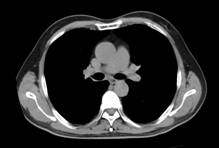

刘××,男,57岁,下肢静脉造影显示混合型DVT,血栓充盈整个左下肢深静脉(图1a~c)。经左股静脉置管后溶栓治疗,10日后血栓完全溶解,再次造影显示左下肢深静脉血流通畅(图2a~c)。

图1a 图1b 图1c

图2a 图2b 图2c